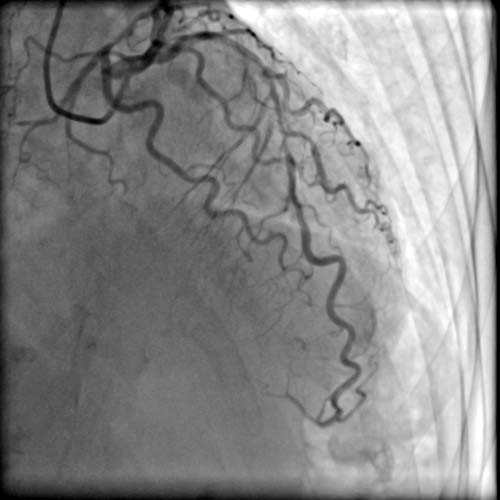

患者杨老先生今年87岁,因反复胸闷胸痛多次在外院住院治疗,外院冠脉造影检查提示“左前降支近段至中段严重钙化,近段狭窄最重处达95%”,手术风险极大。外院予以药物保守治疗后,患者仍时有胸痛发作,服药后症状缓解不明显,痛苦不堪。经当地医院推荐,患者到苑海涛主任处求助。

术前,苑海涛主任带领团队成员共同讨论制定手术方案,结合患者冠脉造影结果,拟对前降支钙化病变进行冠脉旋磨术及支架置入术。

患者高龄,冠脉钙化严重,使得手术难度大、风险高,对操作者的技术及经验提出了更高要求。经过苑海涛主任大胆细致的旋磨治疗,前降支病变顺利开通并成功植入支架。术后,患者胸痛等症状明显缓解,顺利出院。

苑海涛主任介绍,钙化病变是所有介入医生都感到头痛的“硬骨头”,对付如石头般坚硬的斑块,常规的球囊、支架扩张技术难以充分扩张病变。而冠状动脉旋磨术则是处理钙化病变的有效手段,通过高速旋转带有金刚石颗粒的旋磨头对斑块进行研磨销蚀,在血管内开“隧道”,以此解决冠脉介入治疗。冠脉内旋磨术操作难度大、风险高,要求介入医生和团队必须有高超的技艺和默契的配合,尤其是年龄超过70岁的患者,脏器功能更差,冠脉旋磨对术者的心理能力和技术水平都是极大的考验。